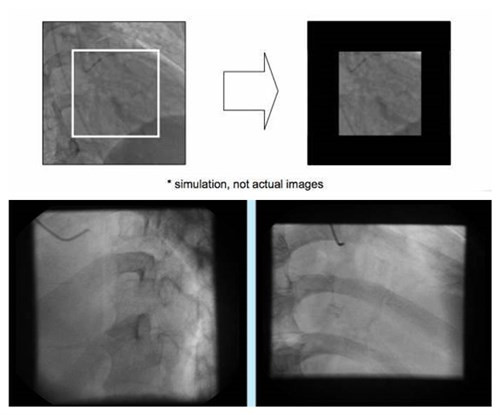

3.准直校正

准直器是用来产生合适照射视野的机械运动部件,安装机器的时候需要跟工程师密切沟通,做好准直校正,我们平时要做好检查工作(

图3 准直作用:缩小准直器照射径,降低医患剂量)。